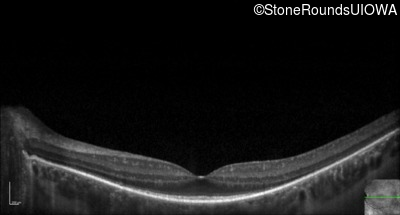

Optical Coherence Tomography - Left - 20/32 -1

Exemplar / OCT Stack

OCT Stack